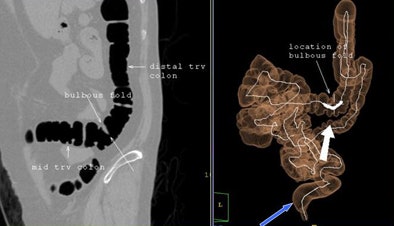

![]() |

| A woman with prior hysterectomy and incomplete colonoscopy demonstrates tortuous colon anatomy, including a bulbous fold, and a redundant sigmoid colon that has prolapsed into the pelvic inlet, preventing the endoscopist from advancing the colonoscope. |

"What is the cause of this increased rate of incomplete or failed colonoscopy in women following hysterectomy? Is it due to sigmoid angulation, is it tethering and adhesions and redundant colon? We're not really sure," Zafar said. "These are issues for further study."

For example, the group has not yet compared colonic anatomy in patients with hysterectomy versus no hysterectomy, Zafar said in response to a question from the audience. "Some of these women have incredibly tortuous colons, not just the sigmoid colon," she said. "We need to go back and look."